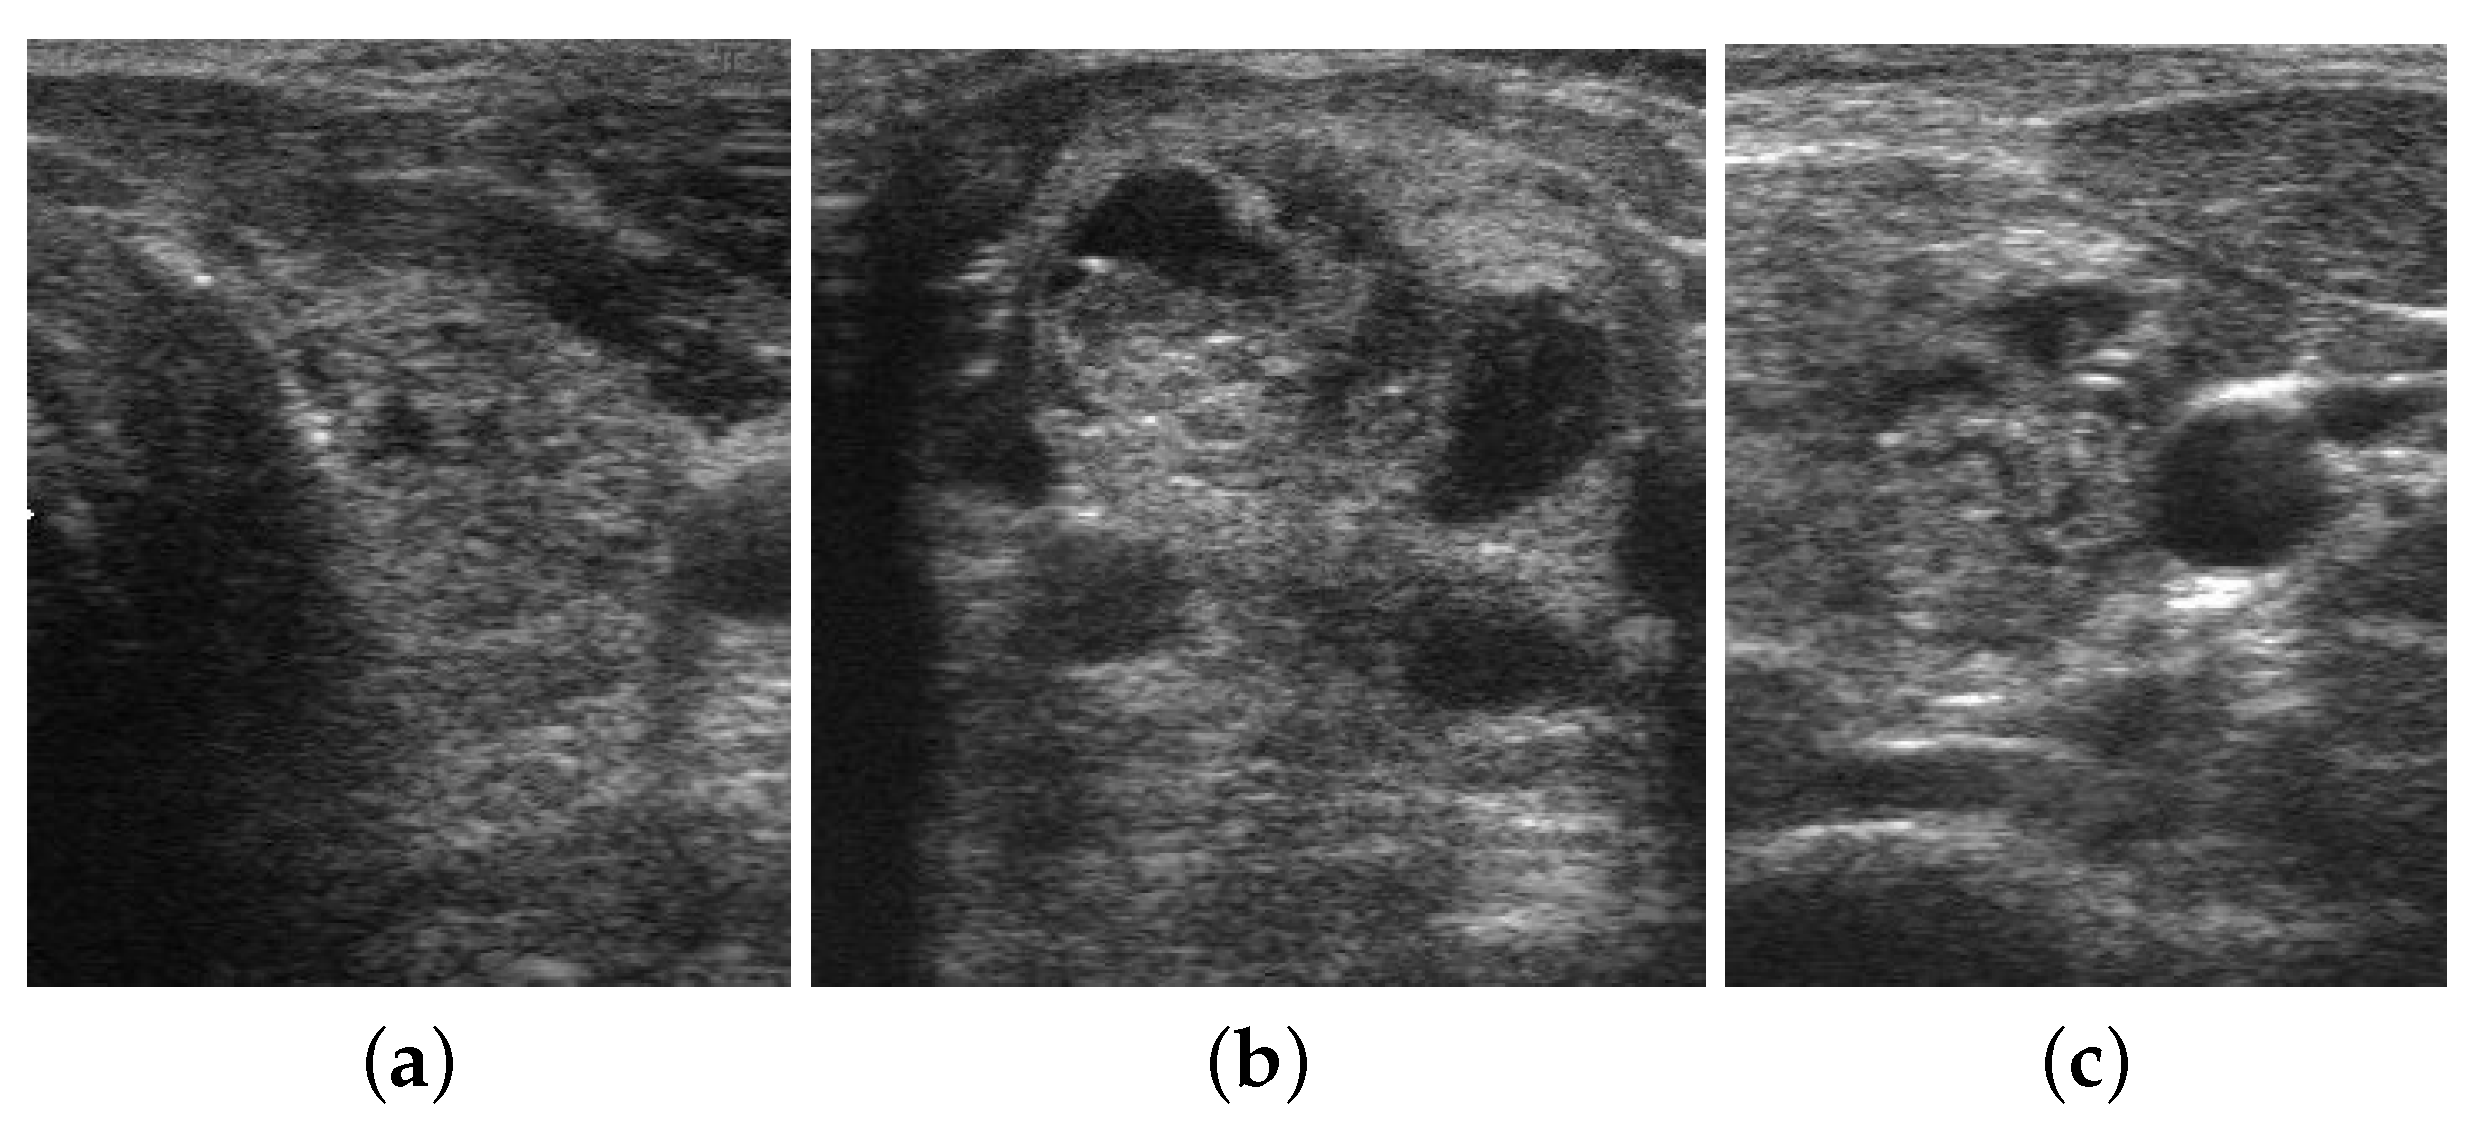

For the thyroid nodule dataset, we initialized the proposed network with pre-trained weights taken from the breast ultrasound image classification model. We utilized an open-source thyroid nodule image dataset named DDTI. It contains ultrasound nodular thyroid images. Currently, DDTI contains 980 ultrasound images in total (322 images exhibit malignant nature and 658 images exhibit benign nature), around for the training set and around for the validation and test sets. This dataset was collected and published by Pedrazza et al. in 2015 [50,51,52]. The proposed database includes B-mode ultrasound images with a complete annotation and diagnostic description of suspicious thyroid lesions by expert radiologists [53]. The dataset includes several types of lesions like thyroiditis, cystic, adenomas, and carcinomas, and accurate lesion delineation is provided in an XML format. The diagnostic confirmation of malignant lesions was confirmed by their histopathological analysis [53]. Some sample images from DDTI dataset are given in Figure 10.

Figure 10.

Sample images from the DDTI dataset. The first image (a) and the last image (c) represent benign nodules and the middle image (b) represents a malignant nodule.